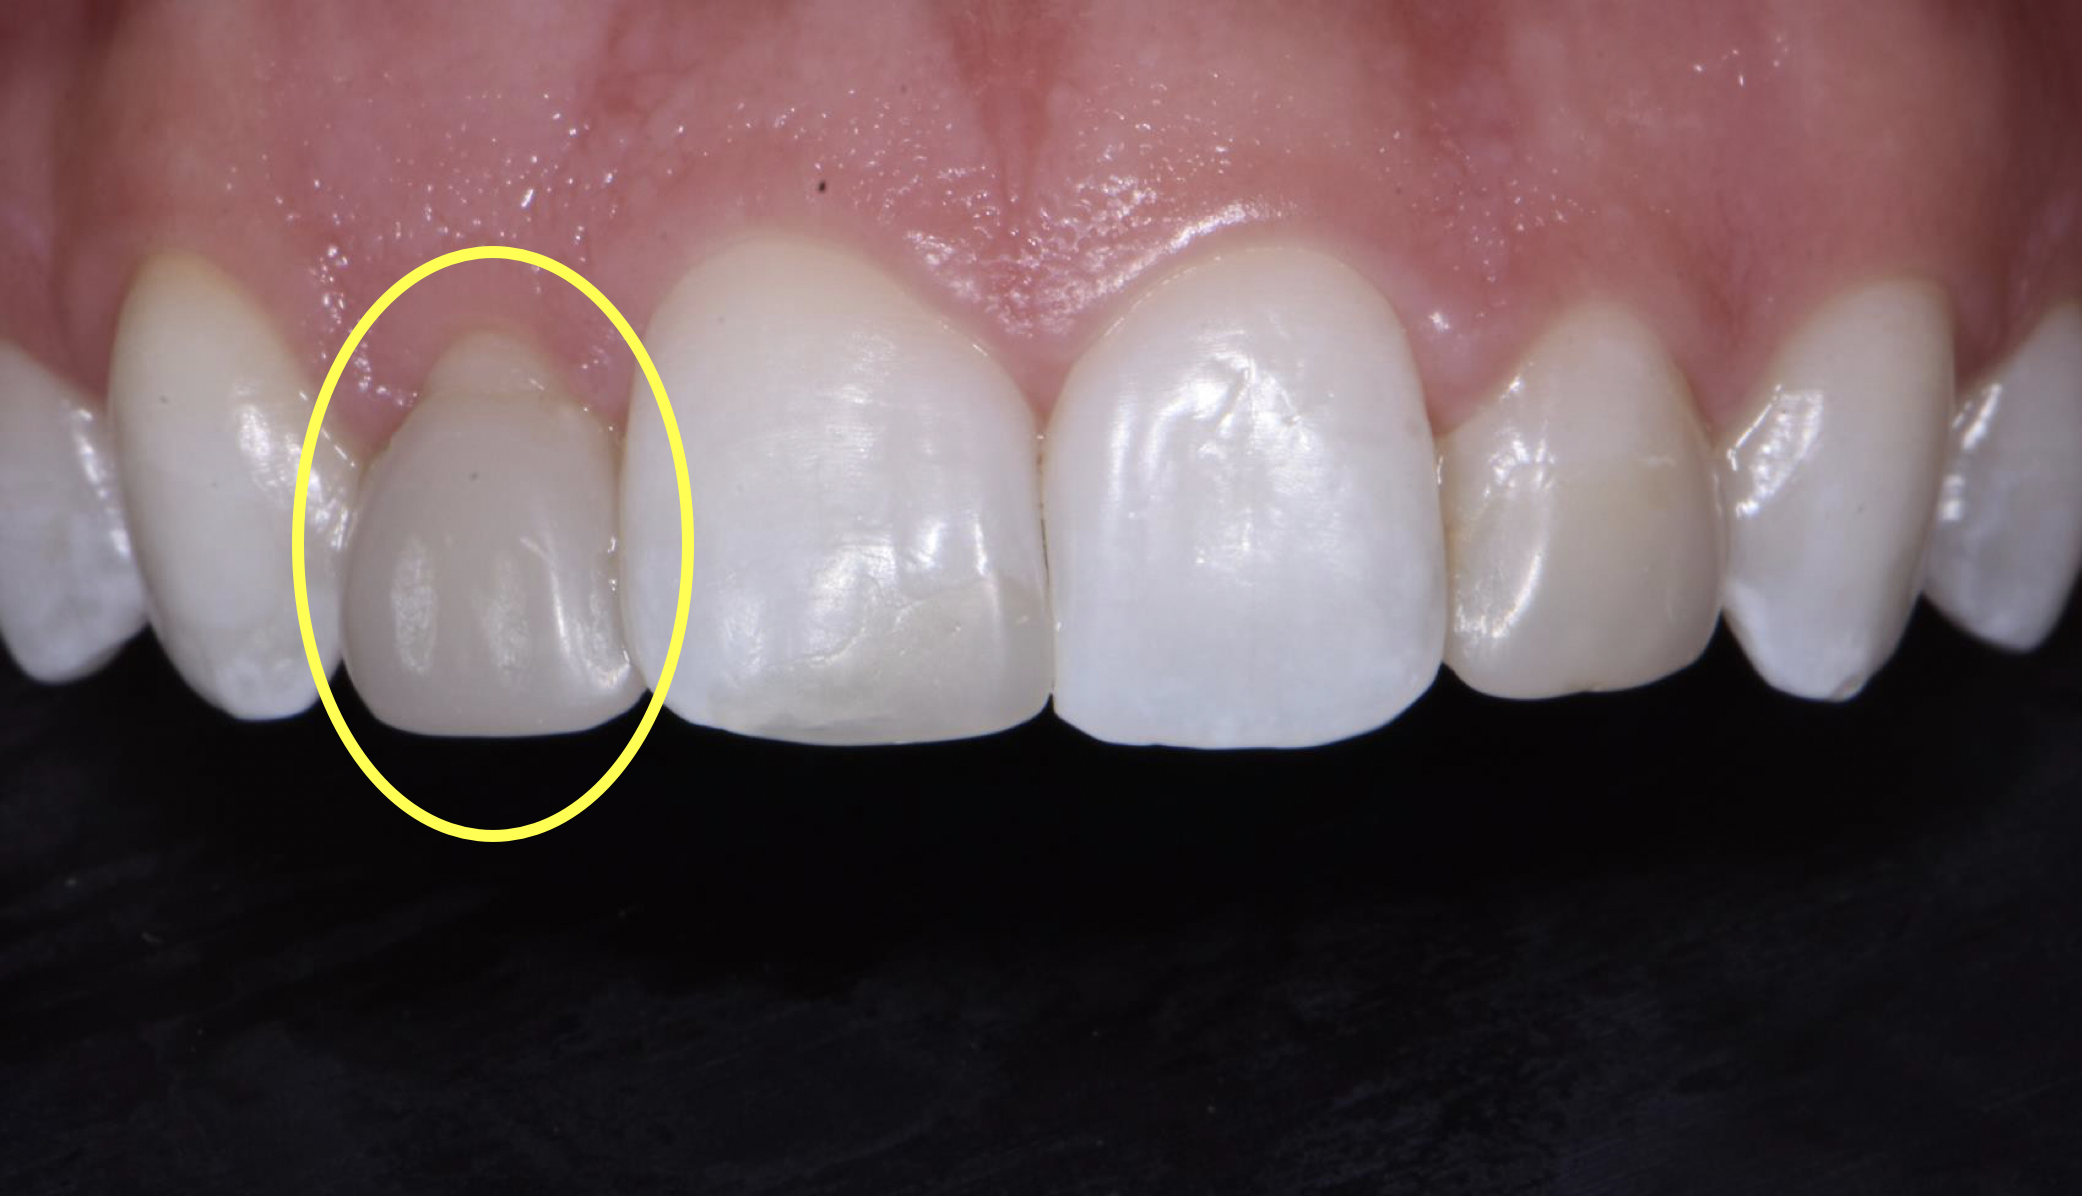

Fig 6. An asymmetrical black triangle calls for the practitioner to add more volume to one tooth and less to another.

Figure 6

When a black triangle is being treated, both the shape and the size should be assessed (Figure 6). For a symmetrical black triangle, two matrices of the same size should be chosen to evenly distribute the black triangle between two teeth and avoid creation of a cant. An asymmetrical black triangle calls for mixing matrices so the practitioner can selectively add more volume to one tooth and less to another to maintain a vertical line (Figure 7). When selecting matrices, large incisor matrices should be used for maxillary central incisors and cuspids, while small incisor matrices for maxillary lateral incisors and mandibular central and lateral incisors.4 The selected matrices should then be inserted and checked for full seating and alignment. The incisal edge of the matrices is a visual clue as to whether those matrices are seated equally.